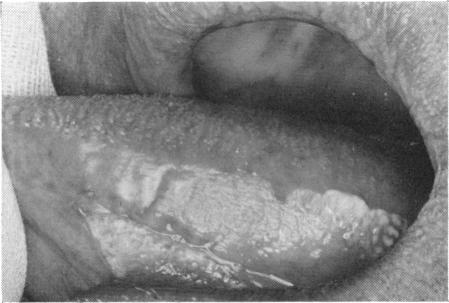

COOKE B E

Ann R Coll Surg Engl. 1964 Jun;34(6):370-83.